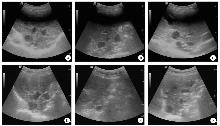

Objective To evaluate the efficacy of albendazole (ABZ) and pyronaridine (PND) for the treatment of cystic echinococcosis (CE) in sheep. Methods B-mode ultrasonography was performed in sheep from the central Tianshan Mountains regions in Xinjiang Uygur Autonomous Region, and 18 sheep with typical CE characteristics and comparable prevalence were selected, and randomized into the control group, the ABZ group and PND group using a completely randomized design. Sheep in the ABZ group were fed baits containing ABZ (0.4 g ABZ in 1 g feed bait), and sheep in the PND group were fed baits containing PND (0.2 g PND in 1 g feed bait), while sheep in the control group were fed drug-free feed baits. Drugs were administered continuously for 30 days, followed by a 30-day observation period after drug discontinuation. Whole-liver scans were performed on sheep with CE before dosing and 30 days after drug discontinuation, and cyst size was recorded. Sheep hearts, livers, spleen, lungs, and kidneys were collected and weighed 30 days after drug discontinuation. Whole blood samples were collected for routine blood tests and blood biochemistry analysis. Liver cysts were sampled, and classified into fertile cysts, infertile cysts, and calcified cysts based on the cyst appearance and its contents. The number and weight of different types of cysts were recorded. Hepatic tissues were prepared into paraffin-embedded sections, subjected to hematoxylin-eosin (HE) staining for pathological examinations, and evaluated for scoring of inflammatory cell infiltration. All statistical analyses were performed using the software IBM SPSS Statistics 20. Multiple comparisons were conducted using one-way analysis of variance or nonparametric tests, while intergroup comparisons of cyst types were assessed using chi-square test. Results B-mode ultrasonography measured no significant difference in the diameter of liver cysts among the control group [(2.86 ± 0.94) cm], ABZ group [(2.58 ± 0.83) cm], and PND group [(2.65 ± 0.81) cm] prior to oral administration (F = 0.090, P > 0.05). The diameters of cysts were (0.41 ± 0.30) cm in the ABZ group and (0.85 ± 0.24) cm in the PND group 30 days after drug discontinuation, which were significantly smaller than in the control group [(3.03 ± 0.42) cm] (F = 110.398, P < 0.01). The sheep liver weights were (0.98 ± 0.20), (0.74 ± 0.16), and (0.61 ± 0.30) kg in the control group, ABZ group, and PND group 30 days after drug discontinuation, respectively (F = 3.989, P < 0.05). There were no significant differences in routine blood and biochemical parameters among the control, ABZ, and PND groups (all P > 0.05). The gross cyst weights were (0.02 ± 0.05) kg and (0.05 ± 0.08) kg in the ABZ and PND groups 30 days after drug discontinuation, which were significantly lower than in the control group [(0.17 ± 0.06) kg] (F = 7.835, P < 0.01). The proportions of fertile cysts, infertile cysts, and calcified cysts were 63.16% (48/76), 17.10% (13/76), and 19.74% (15/76) in the control group, and 23.08% (12/52), 1.92% (1/52), and 75.00% (39/52) in the ABZ group, respectively (χ2 = 39.439, P < 0.01), with reduced proportions of fertile and infertile cysts and an increased proportion of calcified cysts in the ABZ group. The proportions of fertile cysts, infertile cysts, and calcified cysts were 31.03% (18/58), 6.90% (4/58), and 62.07% (36/58) in the PND group, which showed significant differences relative to the control group (χ2 = 25.083, P < 0.01), with an reduced proportion of fertile cysts and an increased proportion of calcified cysts in the PND group. The scores of inflammatory cell infiltration were 1.06 ± 0.25 and 1.50 ± 0.28 in the ABZ and PND groups 30 days after drug discontinuation, which were both significantly lower than in the control group (2.72 ± 0.44) (F = 39.780, P < 0.01). Conclusion Oral administration of ABZ or PND may reduce the number of fertile cysts in livers of sheep with CE and alleviate the severity of inflammatory cell infiltration, indicating that both chemicals are effective against sheep CE.